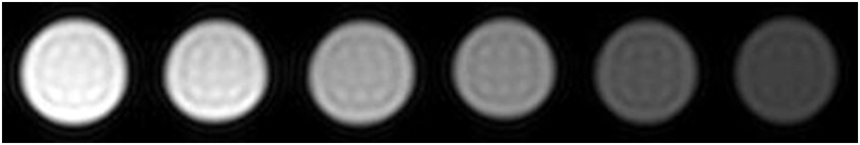

磁性纳米材料作为磁共振(MRI)造影剂的应用